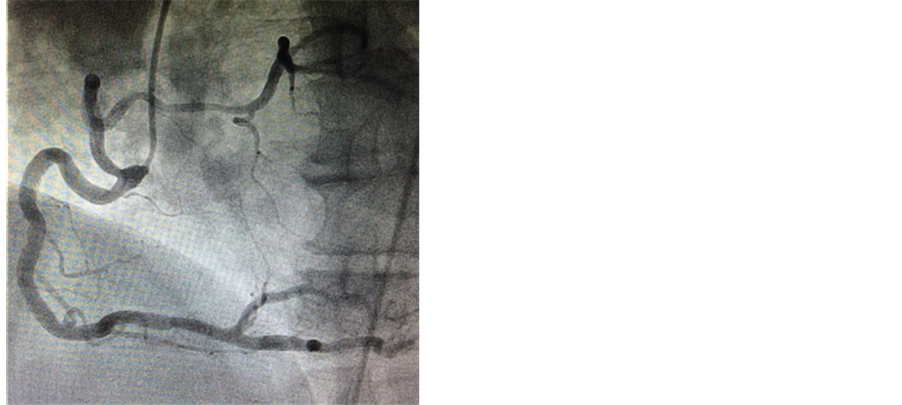

A 57-year-old man (body surface area, 1.9 m2) presented with exertional dyspnea. Transthoracic echocardiography revealed a calcified bicuspid aortic valve (Figure 1) with a mean pressure gradient of 63 mmHg and a calculated aortic valve area of 0.78 cm2, consistent with severe stenosis. Left ventricular ejection fraction was preserved at 65%. Preoperative coronary angiography demonstrated a single coronary artery above the right coronary cusp. The left coronary artery originated from the proximal portion of the right coronary artery (Figure 2). Three-dimensional computed tomography angiography demonstrated that the left coronary artery traveled anteriorly from its anomalous origin and across the conus arteriosus before anatomically correct bifurcation into left anterior descending and left circumflex vessels (Figure 3). No associated coronary artery disease was observed. Aortic valve replacement was performed via full median sternotomy. The ascending aorta was cannulated, and venous cannulation was performed through the right atrium. The patient’s core body temperature was slowly decreased to 35.5˚C. Myocardial protection was achieved using a combination of antegrade and retrograde cold bloodcardioplegia. The annulus sized to a 23 valve. The right coronary artery ostium was identified above the right coronary cusp via preoperative three-dimensional computed tomography angiography. The right coronary artery ostium was only 7 mmabove the annulus. We modified the procedure because of this proximity and the associated risk of coronary ostium occlusion if we set the valve supra-annularly. The 21-mm Aortic Magna Ease Valve (Edwards, Inc., Irvine, CA) was placed intra-annularly using everting sutures. The patient recovered uneventfully and was discharged home on postoperative day 7. He provided written informed consent for publication of this case report and all accompanying images.

Figure 2. Single coronary angiography.